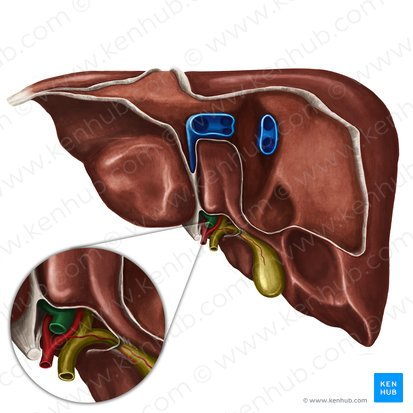

Liver

a large organ located in the upper right abdomen that produces bile, detoxifies blood, and performs many other metabolic functions.

Considered as the largest gland in the body

Right lobe of Liver

The larger of the two main lobes of the liver, located on the right side of the abdomen.

Left lobe of the Liver

The smaller of the two main lobes of the liver, located on the left side of the abdomen.

Quadrate Lobe

A small, quadrilateral lobe of the liver located inferiorly and medially on the visceral surface, bordered by the gallbladder and the fissure for the round ligament.

Caudate Lobe

A small lobe of the liver located posteriorly on the visceral surface, near the inferior vena cava and the fissure for the ligamentum venosum.

Falciform Ligament of the Liver

A broad, thin fold of peritoneum that attaches the liver to the anterior abdominal wall and diaphragm. It also marks the division between the right and left lobes on the anterior surface.

Round Ligament of the Liver

A fibrous cord that represents the remnant of the umbilical vein of the fetus. It is located in the free edge of the falciform ligament.

Gallbladder

A small, pear-shaped organ located beneath the liver that stores and concentrates bile produced by the liver.

Right Hepatic Duct

A duct that carries bile produced by the right lobe of the liver.

Left Hepatic Duct

A duct that carries bile produced by the left lobe of the liver.

Common Hepatic Duct

The duct formed by the union of the right and left hepatic ducts, which carries bile away from the liver.

Cystic Duct

The duct that connects the gallbladder to the common hepatic duct, allowing bile to enter and exit the gallbladder.

Hepatic Artery

A branch of the celiac artery that supplies oxygenated blood to the liver.

Hepatic Portal Vein

A large vein that carries deoxygenated but nutrient-rich blood from the digestive organs (stomach, intestines, spleen, pancreas) to the liver for processing.

Inferior Vena Cava

A large vein that carries deoxygenated blood from the lower and middle body back to the heart.